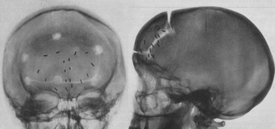

Les trépanations, dont les premières remonteraient au néolithique, comptent probablement parmi les gestes les plus anciens dans le traitement de la douleur [1] et les temps ne sont pas si lointains où des tribus réalisaient cette intervention crânienne pour « libérer l’esprit » ou soigner certaines céphalées [2]. Exception faite de ces interventions ancestrales — relevant davantage de la magie que de la médecine — on observe que l’histoire de la chirurgie ablative suit un fil relativement logique en remontant le long des nerfs jusqu’aux centres intégrateurs comme le soulignait le neurochirurgien Lyonnais Wertheimer : « dans la mesure où la douleur s’inscrit dans des trajets précis qui, de la périphérie, des membres, du tronc et de la face, comme des viscères, la conduisent aux noyaux thalamiques, il était prévisible que la chirurgie tenterait de s'opposer à cette progression » [3]. Une progression ascendante qui doit autant à la compréhension des voies de la douleur, à la révolution pastorienne qu’aux progrès des techniques de chirurgie et d’anesthésie. Ainsi, de la périphérie vers le cerveau, l’audace des chirurgiens s’est progressivement libérée.